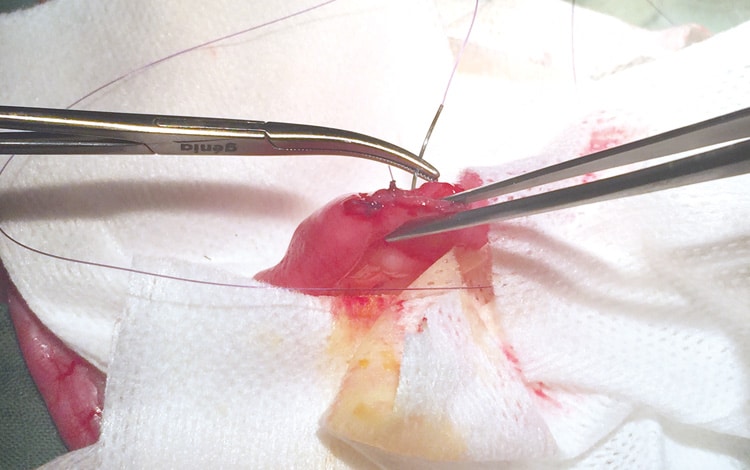

La chirurgie est généralement pratiquée en cas d’occlusion intestinale totale par gastrotomie : ouverture de l’estomac ou entérotomie : ouverture de l’intestin.

Cette dernière s’avère être le seul moyen pour résoudre l’affection sauf si le corps étranger n’est pas vulnérant (qui blesse) et se situe dans la portion haute du tube digestif (estomac, début de l’intestin grêle) et peut être extrait sous endoscopie : une exploration à l’aide d’un endoscope permettant de visualiser l’intérieur du tube digestif et qui nécessite une anesthésie générale.

Chirurgie d’une occlusion intestinale chez un chat :

1 • Radiographie mettant en évidence la présence d’un corps étranger dans l’intestin d’un chat.

2 • Ouverture de l’abdomen et extériorisation de l’anse intestinale occluse.

3 • Incision de la paroi intestinale avec un bistouri.

4 • Retrait du corps étranger de l’intestin à l’aide d’une pince.

5 • Corps étranger extrait.

6 • Suture de la paroi intestinale avec du fil résorbable*.

Un traitement médicamenteux sera adjoint à la chirurgie et à une perfusion afin de réhydrater le chat.